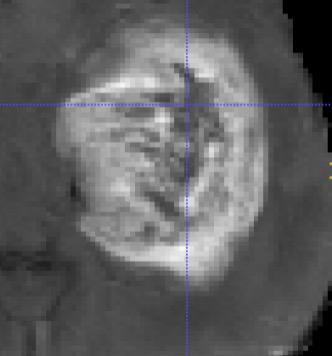

As information sources are usually imperfect, it is necessary to take into account their reliability in multi-source information fusion tasks. In this paper, we propose a new deep framework allowing us to merge multi-MR image segmentation results using the formalism of Dempster-Shafer theory while taking into account the reliability of different modalities relative to different classes. The framework is composed of an encoder-decoder feature extraction module, an evidential segmentation module that computes a belief function at each voxel for each modality, and a multi-modality evidence fusion module, which assigns a vector of discount rates to each modality evidence and combines the discounted evidence using Dempster's rule. The whole framework is trained by minimizing a new loss function based on a discounted Dice index to increase segmentation accuracy and reliability. The method was evaluated on the BraTs 2021 database of 1251 patients with brain tumors. Quantitative and qualitative results show that our method outperforms the state of the art, and implements an effective new idea for merging multi-information within deep neural networks.